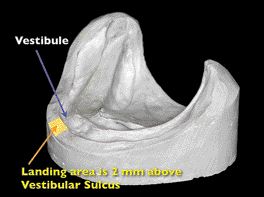

Maintaining Proper Access of the Maxillary and Mandibular Ridges During Impression Making

It has been reported in several published articles that prosthodontic success is contingent on patient cooperation both during treatment and after care. As dentists we all know that one of the most difficult procedures is trying to make an impression on the edentulous patient. Some patients have extremely strong muscles and we are fighting to … Read more